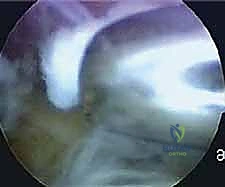

الخطوة الثالثة: إدخال الكاميرا والأدوات الدقيقة

يتم إدخال كاميرا دقيقة جداً (بقطر 4 ملم) مزودة بتقنية تصوير 4K عالية الوضوح عبر أحد الثقوب. تعرض هذه الكاميرا صورة مكبرة وواضحة جداً للأنسجة الداخلية على شاشة كبيرة، مما يتيح للدكتور هطيف رؤية المفصل بتفاصيل لا يمكن للعين المجردة رؤيتها. يتم إدخال أدوات الجراحة الدقيقة (Micro-instruments) عبر الثقب الآخر.

الخطوة الرابعة: تحديد سبب الانحشار وإزالته

باستخدام أدوات متخصصة، يقوم الدكتور هطيف بتنظيف الأنسجة الملتهبة، ثم يحدد موقع العظمة المثلثية (Os Trigonum) أو بروز ستيدا المكسور. بمهارة فائقة، يتم تحرير هذه العظمة من الأنسجة المحيطة بها واستئصالها بالكامل وإخراجها من المفصل. يتم أيضاً التأكد من تحرير وتر العضلة المثنية الطويلة للإصبع الكبير (FHL) لضمان حركته بسلاسة دون أي احتكاك.